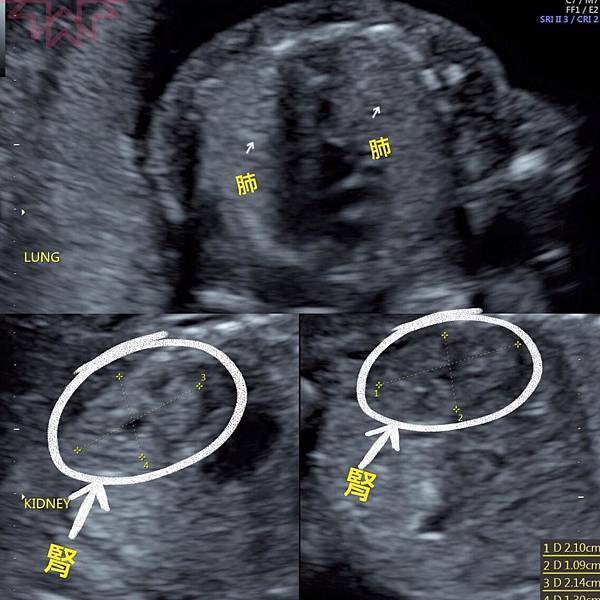

而且姿勢很配合,順利地從頭、眼、鼻、唇、四肢、手指腳趾、心肝脾肺腎胃膽都看得一清二楚

判別超音波真的好難啊,我們外行人怎麼看都是黑白雜訊

技術師和醫生竟然可以從這小黑洞看出是肺還是腎臟實在是太厲害了